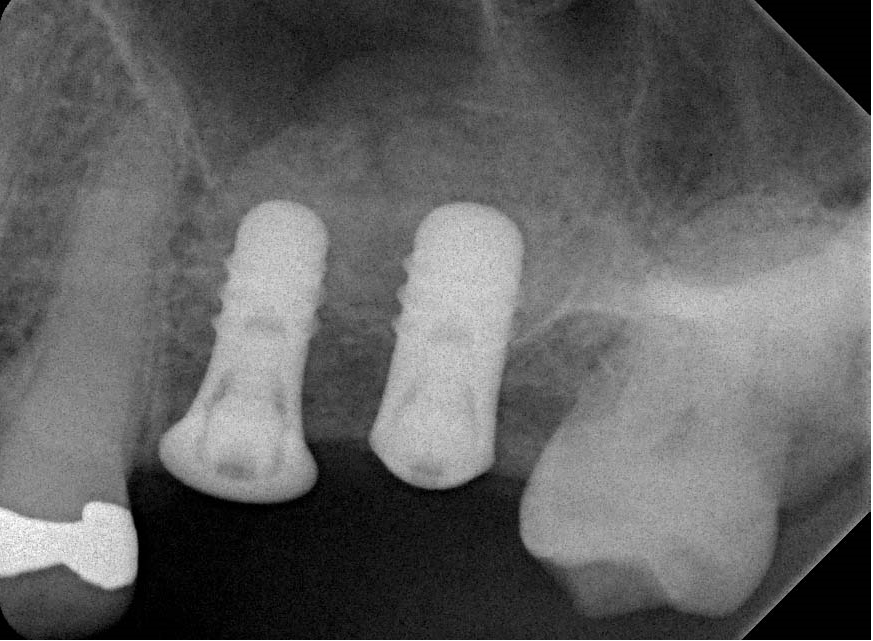

Using a two stage surgical approach, initial depth was confirmed with intraoperative radiographs using 2.8mm depth gauges.